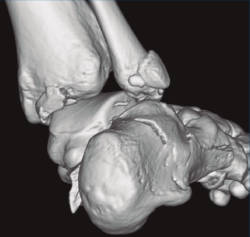

Figura 2. Fractura maléolo peroneo y tibial posterior. Trazo entre fragmento anteromedial y posterolateral.

Se trata de un varón de 19 años que ingresa en reanimación tras precipitarse desde una altura de aproximadamente 10 metros. El paciente presenta una fractura estallido de L3 con afectación del canal medular junto con una fractura del vértice inferior de L4, así como una fractura luxación de calcáneo, asociada a una fractura del maléolo peroneo y del maléolo tibial posterior (Figuras 1 a 6) diagnosticadas mediante TC total body (por eso no se dispone de radiografías simples al momento del ingreso). Como podemos comprobar, se trata de una fractura de doble trazo de tipo hundimiento/depresión de la carilla articular (Figuras 5 y 6).

Figura 4. Luxación fragmento posterolateral.